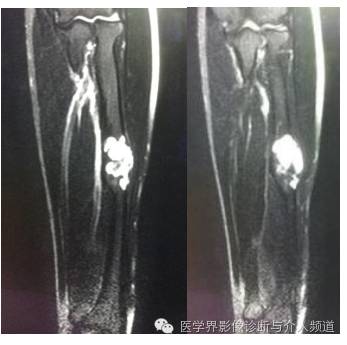

T2WI

MR:一般呈多囊状改变,37%-87.5%的病例囊内有液液平面,在扫描前保持不动10分钟较容易显示。T2WI上液平面上层一般为高信号,可能为血清液或高铁血红蛋白;下层为低信号,可能是细胞及碎裂细胞产物。